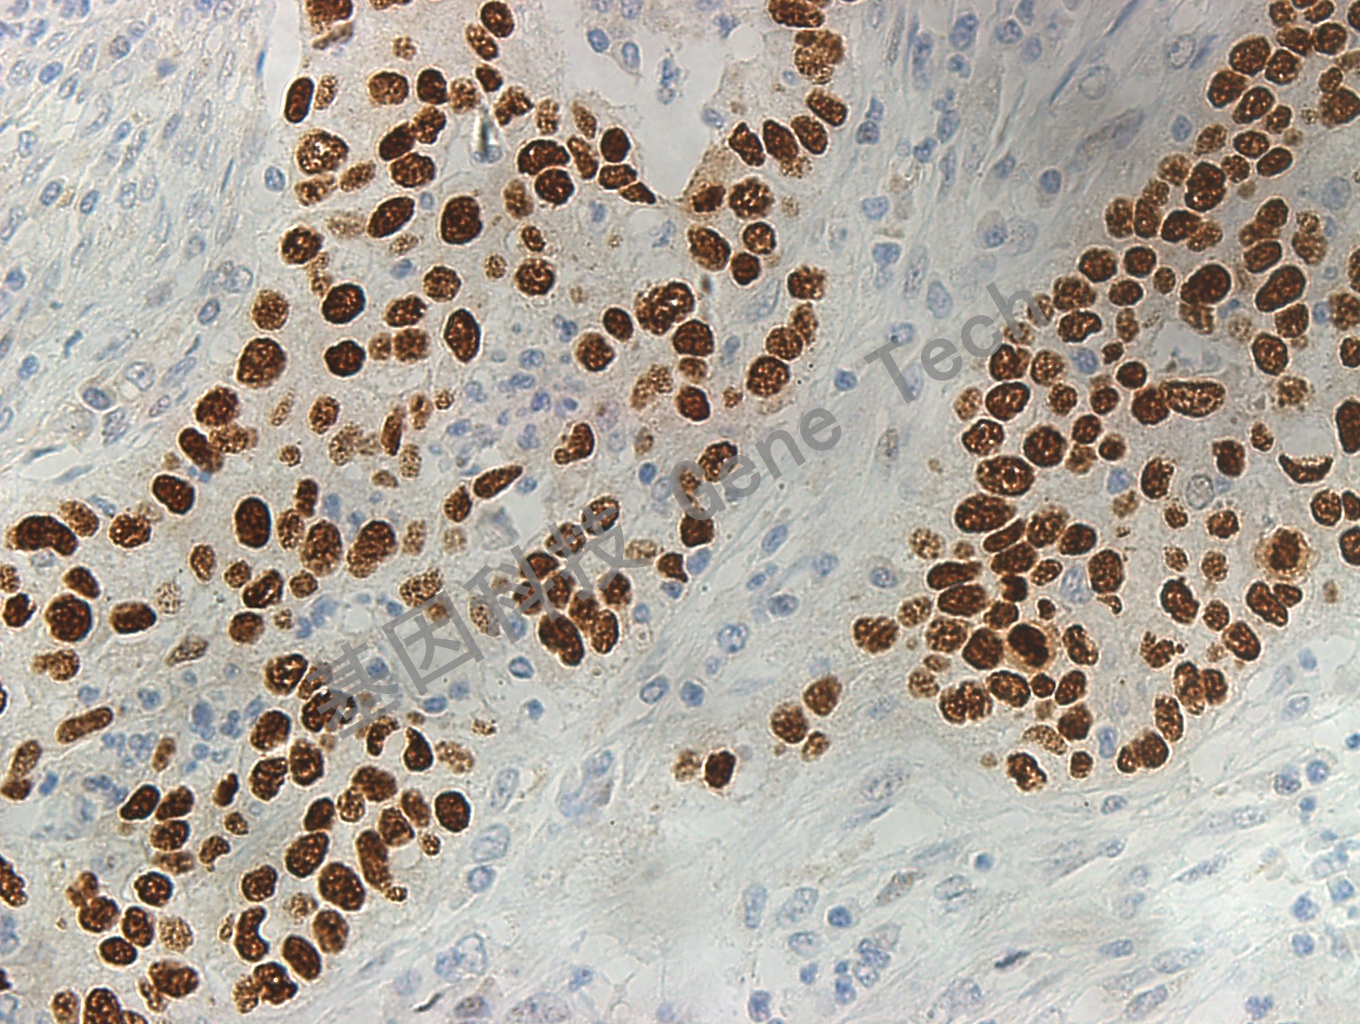

| 預處理:高pH熱修復 | 陽性部位:細胞核 | 陽性對照:肺鱗癌 |

| 簡介:p40(△ Np63)是 p63 蛋白的亞型之一,在日常病理診斷工作中 p63 被廣泛用于肺癌的分型,在肺鱗癌中有很高的敏感性,但也部分表達肺鱗癌,同 p63 相比而言 p40 在肺鱗癌中有著同 p63 抗體類似的高敏感性,但在肺腺癌中罕見表達。故 p40 被推薦用于肺鱗癌和肺腺癌的鑒別診斷。 | ||

| 肺鱗癌石蠟切片,用 p40(GT2531)染色,細胞核陽性,DAB 顯色。 | ||